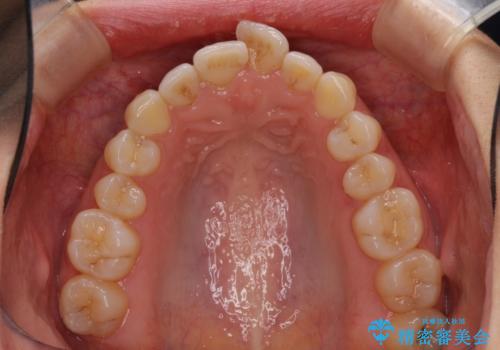

口が閉じにくい 1本飛び出した前歯の矯正治療

- 1本飛び出した前歯を治したいとのことで来院された患者様です。

歯列全体の拡大とIPR(歯と歯の間を削る)によってデコボコが解消するようにし、さらにゴムかけを活用して右側の咬み合わせ位置を変えるように設計し、インビザラインにより治療を行うこととしました。

後方移動に際し、上下顎の親知らずは3本とも抜歯することとしました。